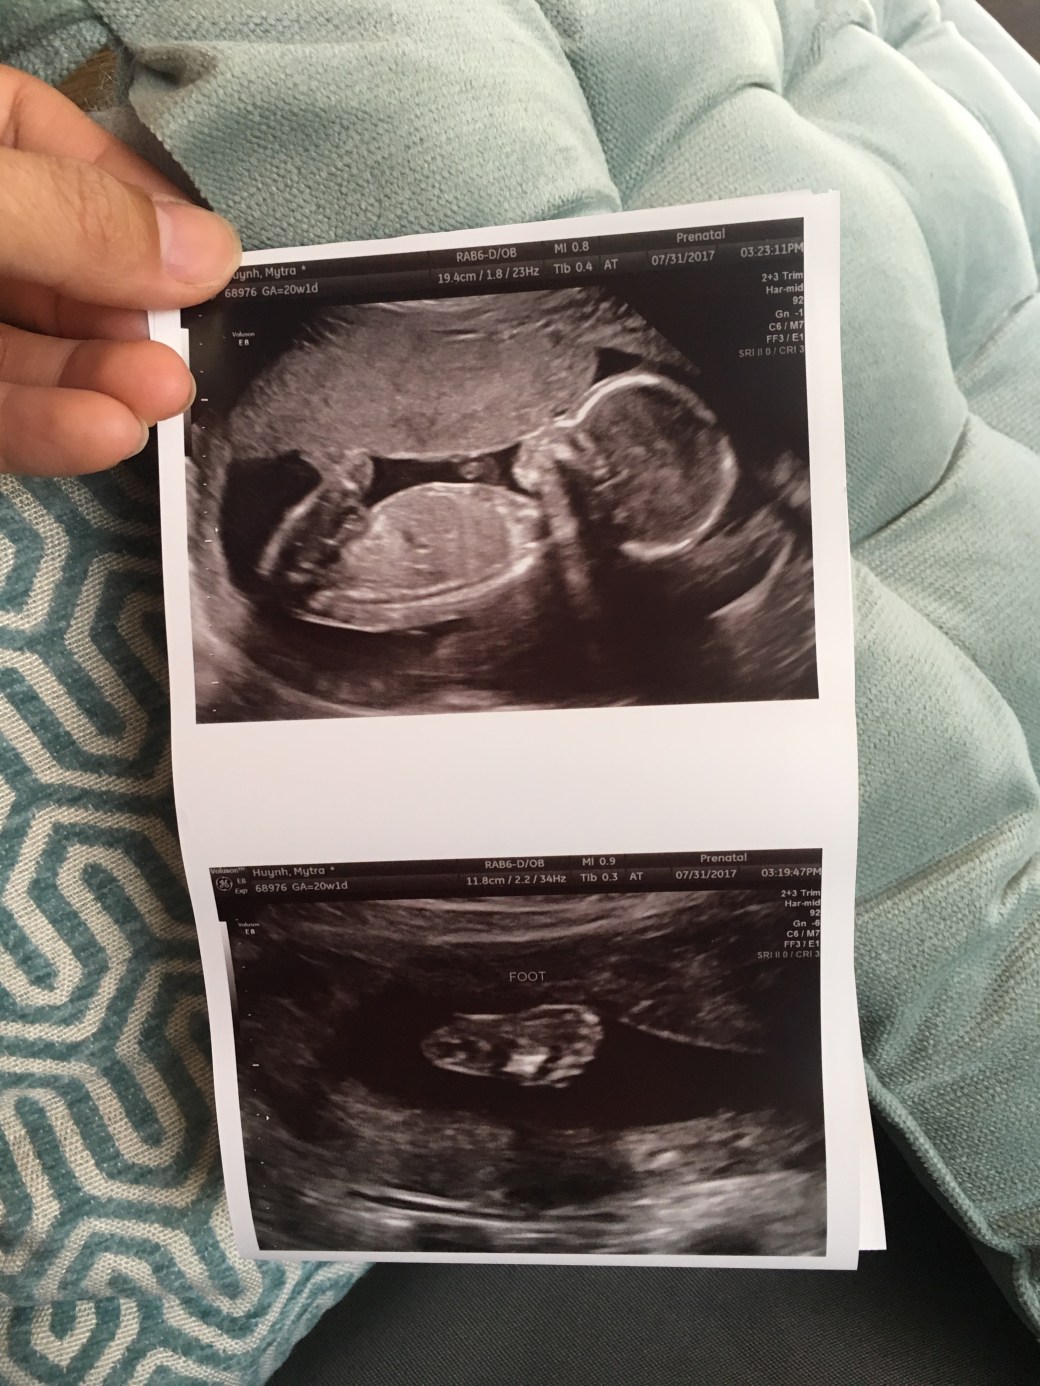

Thank you for being so good to Mommy. Last week when the Doctor said that you weigh in the 75th percentile of babies in your group, we were so happy that we nearly cried. You, my little child, weigh more than 75% of the other kids in your category. Wah!!!!! I am so proud!